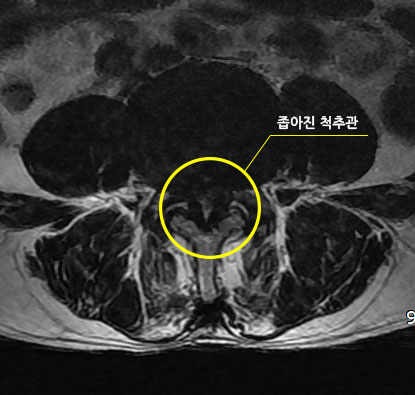

용인경추관협착증 신체에 문제가 생기면 아픈 증상과 함께 불편한 증상으로 많은 스트레스를 받게 됩니다. 특히 경추관협착증은 척수가 지나가는 중심관과 신경근이 지나는 추간공이 좁아져 여러 가지 불편함이 생깁니다. 경추관 협착증을 앓고 있을 때는 다양한 증상이 발생할 수 있습니다. 경추관 협착증일 때는 허리가 아플 수 있습니다. 경추관협착증은 여러 원인으로 여러 부위에 신경증상이 나타나기 때문에 많은 불편이 생깁니다. 척수는 뇌에서 팔, 다리까지 신경이 연결되어 있기 때문에 이상이 생기면 생활에 큰 지장을 초래할 수 있습니다.

용인경추관협착증, 경추관협착증은 신경이 압박받을 수 있으므로 관리에 신경을 써야 합니다. 경추관 협착증은 선천성으로 증상이 나타날 수도 있습니다. 척추관이 좁아지는 것이 원인으로 불편한 증상이 발생할 수 있습니다. 추관협착증은 척추뼈 사이의 과도한 움직임으로 척추가 불안정할 때 신경을 건드리는 특징이 있습니다. 경추관협착증에 시달리면 목의 갑골에 통증을 유발할 수 있습니다.아픈 증상이 나타나면 일상에 큰 지장을 줄 수 있으므로 초기에 건강관리에 유의해야 합니다.